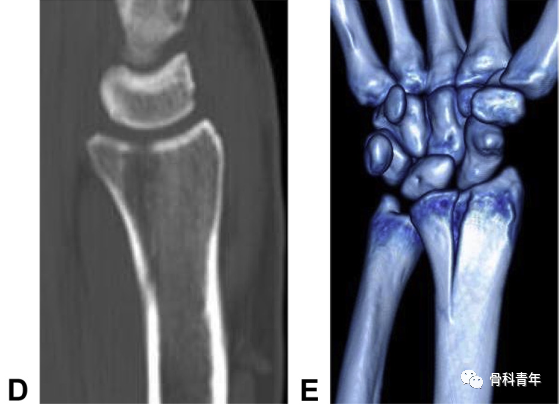

“四面体”型桡骨远端骨折概念:桡骨远端部分关节内骨折,骨折累及桡骨掌尺侧关节面及乙状切迹,横断位上呈三角形,骨折线延伸至桡骨干骺端。该骨折的特殊性体现在桡骨掌尺侧骨块的特殊性。一方面,掌尺侧骨块形成的月骨窝,作为抵抗腕骨向掌侧脱位的物理支撑,该结构的支撑作用消失导致腕关节掌侧脱位;第二,该骨块作为下尺桡关节桡骨关节面的组成部分,恢复其解剖位置是恢复下尺桡稳定性的前提。下图示病例1:典型“四面体”型桡骨远端骨折的影像表现。

在5年的病例中,研究中发现7例该类型骨折。在手术指征上,对上图病例1在内的3例无移位骨折病例,初次行保守治疗,但在随访过程中均出现骨折移位,而进行内固定手术;提示该类型骨折的不稳定性高,再移位风险高,手术指征强。在治疗上,2例采用传统桡侧腕屈肌入路钢板螺钉内固定,其中1例内固定失效骨块移位,采用掌尺侧入路,柱钢板特异性固定中柱翻修。出现内固定失效病例后,其后的5例病例均采用掌尺侧入路2.0mm或2.4mm钢板固定